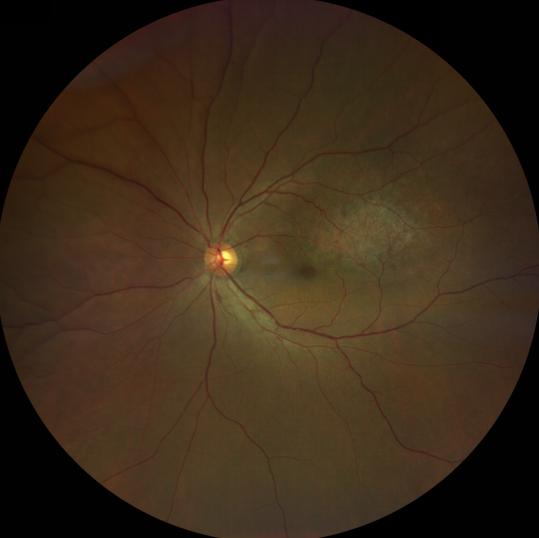

脈絡(luò)膜黑色素瘤是成年人常見的眼內(nèi)惡性腫瘤,其患病率在我國居眼內(nèi)惡性腫瘤的第二位,僅次于視網(wǎng)膜母細胞瘤。其惡性程度高,不僅可致患者喪失視力,而且嚴重威脅患者生命,即使在沒有明確轉(zhuǎn)移前摘除患眼眼球,其5年死亡率也有17%-53%。

脈絡(luò)膜黑色素瘤是葡萄膜惡性腫瘤中較多的一種。葡萄膜腫瘤主要發(fā)生于脈絡(luò)膜、睫狀體和虹膜。其中,脈絡(luò)膜腫瘤占80%,睫狀體腫瘤占12%,虹膜腫瘤占8%。惡性程度高的腫瘤主要發(fā)生于脈絡(luò)膜。發(fā)生于睫狀體的腫瘤惡性程度偏低,發(fā)生于虹膜的腫瘤多數(shù)為良性。脈絡(luò)膜黑色素瘤的特點是惡性程度高、易侵襲轉(zhuǎn)移、預(yù)后極差,嚴重威脅患者的視力和生命。其發(fā)病率有種族差異性,以高加索及白種人居多,黑人發(fā)病率低,亞洲人居于中間。

脈絡(luò)膜黑色素瘤患者在發(fā)病早期無眼痛等癥狀,當(dāng)腫瘤較小時較難發(fā)現(xiàn),隨著病程進展,腫瘤增大,發(fā)生滲出性視網(wǎng)膜脫離或累及黃斑,視力下降才就診。

脈絡(luò)膜黑色素瘤惡性程度高,50%的患者會發(fā)生轉(zhuǎn)移,轉(zhuǎn)移到肝、肺等遠處臟器,常見的轉(zhuǎn)移方式是經(jīng)鞏膜導(dǎo)管擴散,經(jīng)視神經(jīng)蔓延者罕見。一旦發(fā)生轉(zhuǎn)移,1年生存率只有10%,即絕大多數(shù)病人在半年至1年間會失去生命。因此,早期診斷和選擇合適的治療方式對有效提高局部腫瘤的控制率、降低腫瘤的遠處轉(zhuǎn)移率、延長患者的生存率具有重要意義。